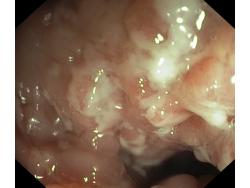

Obrazy endoskopowe

Celiakia